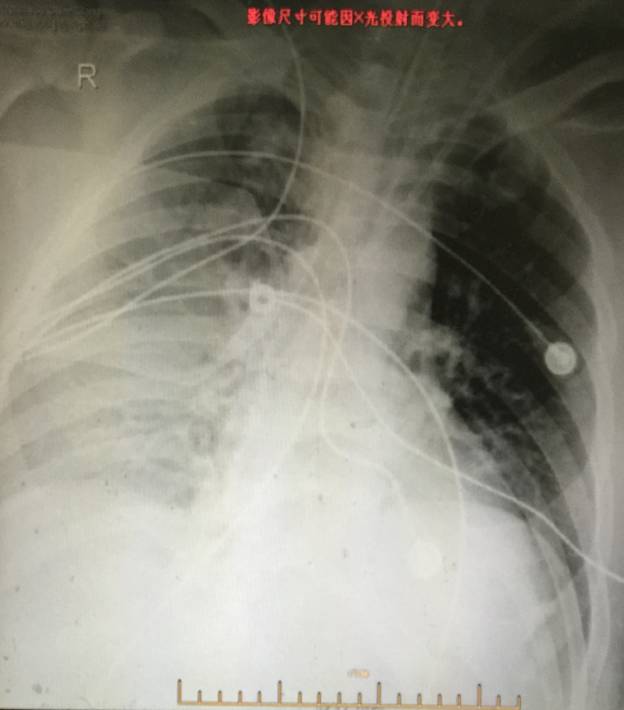

胸片: